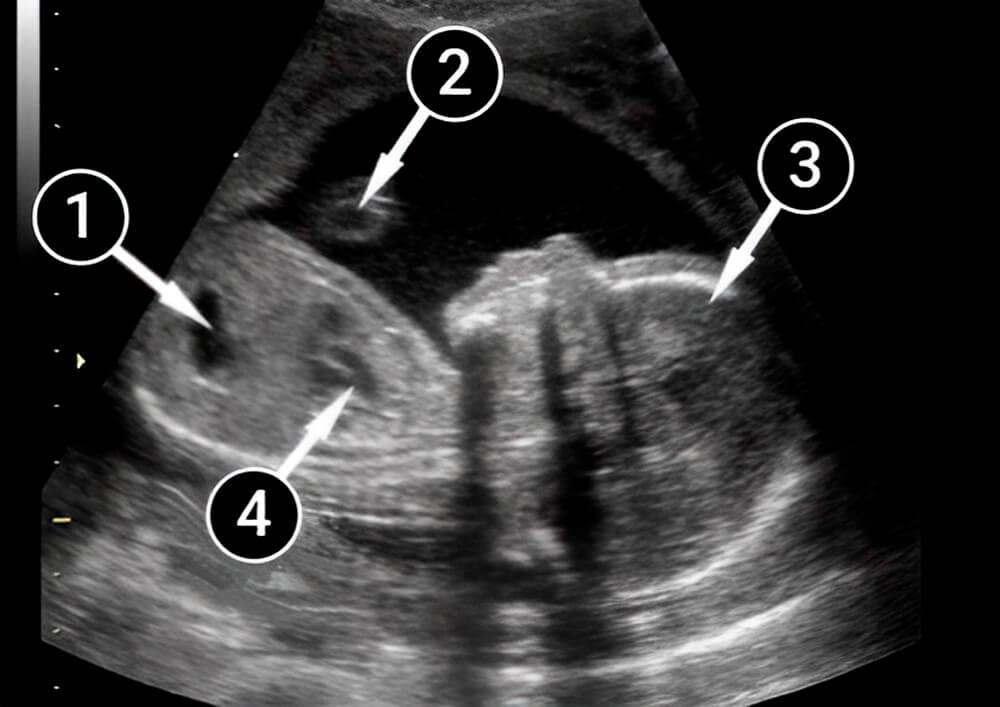

En la siguiente imagen, el corazón está claramente dividido en aurículas y ventrículos. Por encima de la columna vertebral, en la parte inferior de la imagen, el vaso principal (la aorta), apenas se nota.

Asimismo, el estómago es visible con claridad, se aprecia como un óvalo oscuro en la imagen. En lo profundo del líquido amniótico, puedes ver la mano del bebé.

estómago

mano

cabeza

corazón